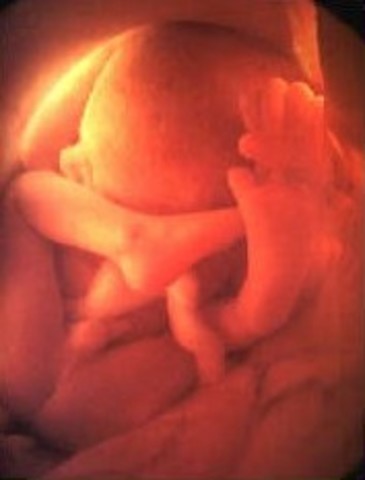

thirtd Trimester

• Week 27

Week 27

third Trimester begins. Fetus is now able to open eyes however still not able to see.

• Week 28

Week 28

Hair is visible through 4D ultrasounds. Milk teeth have started growing under the gums and eyes start to move.